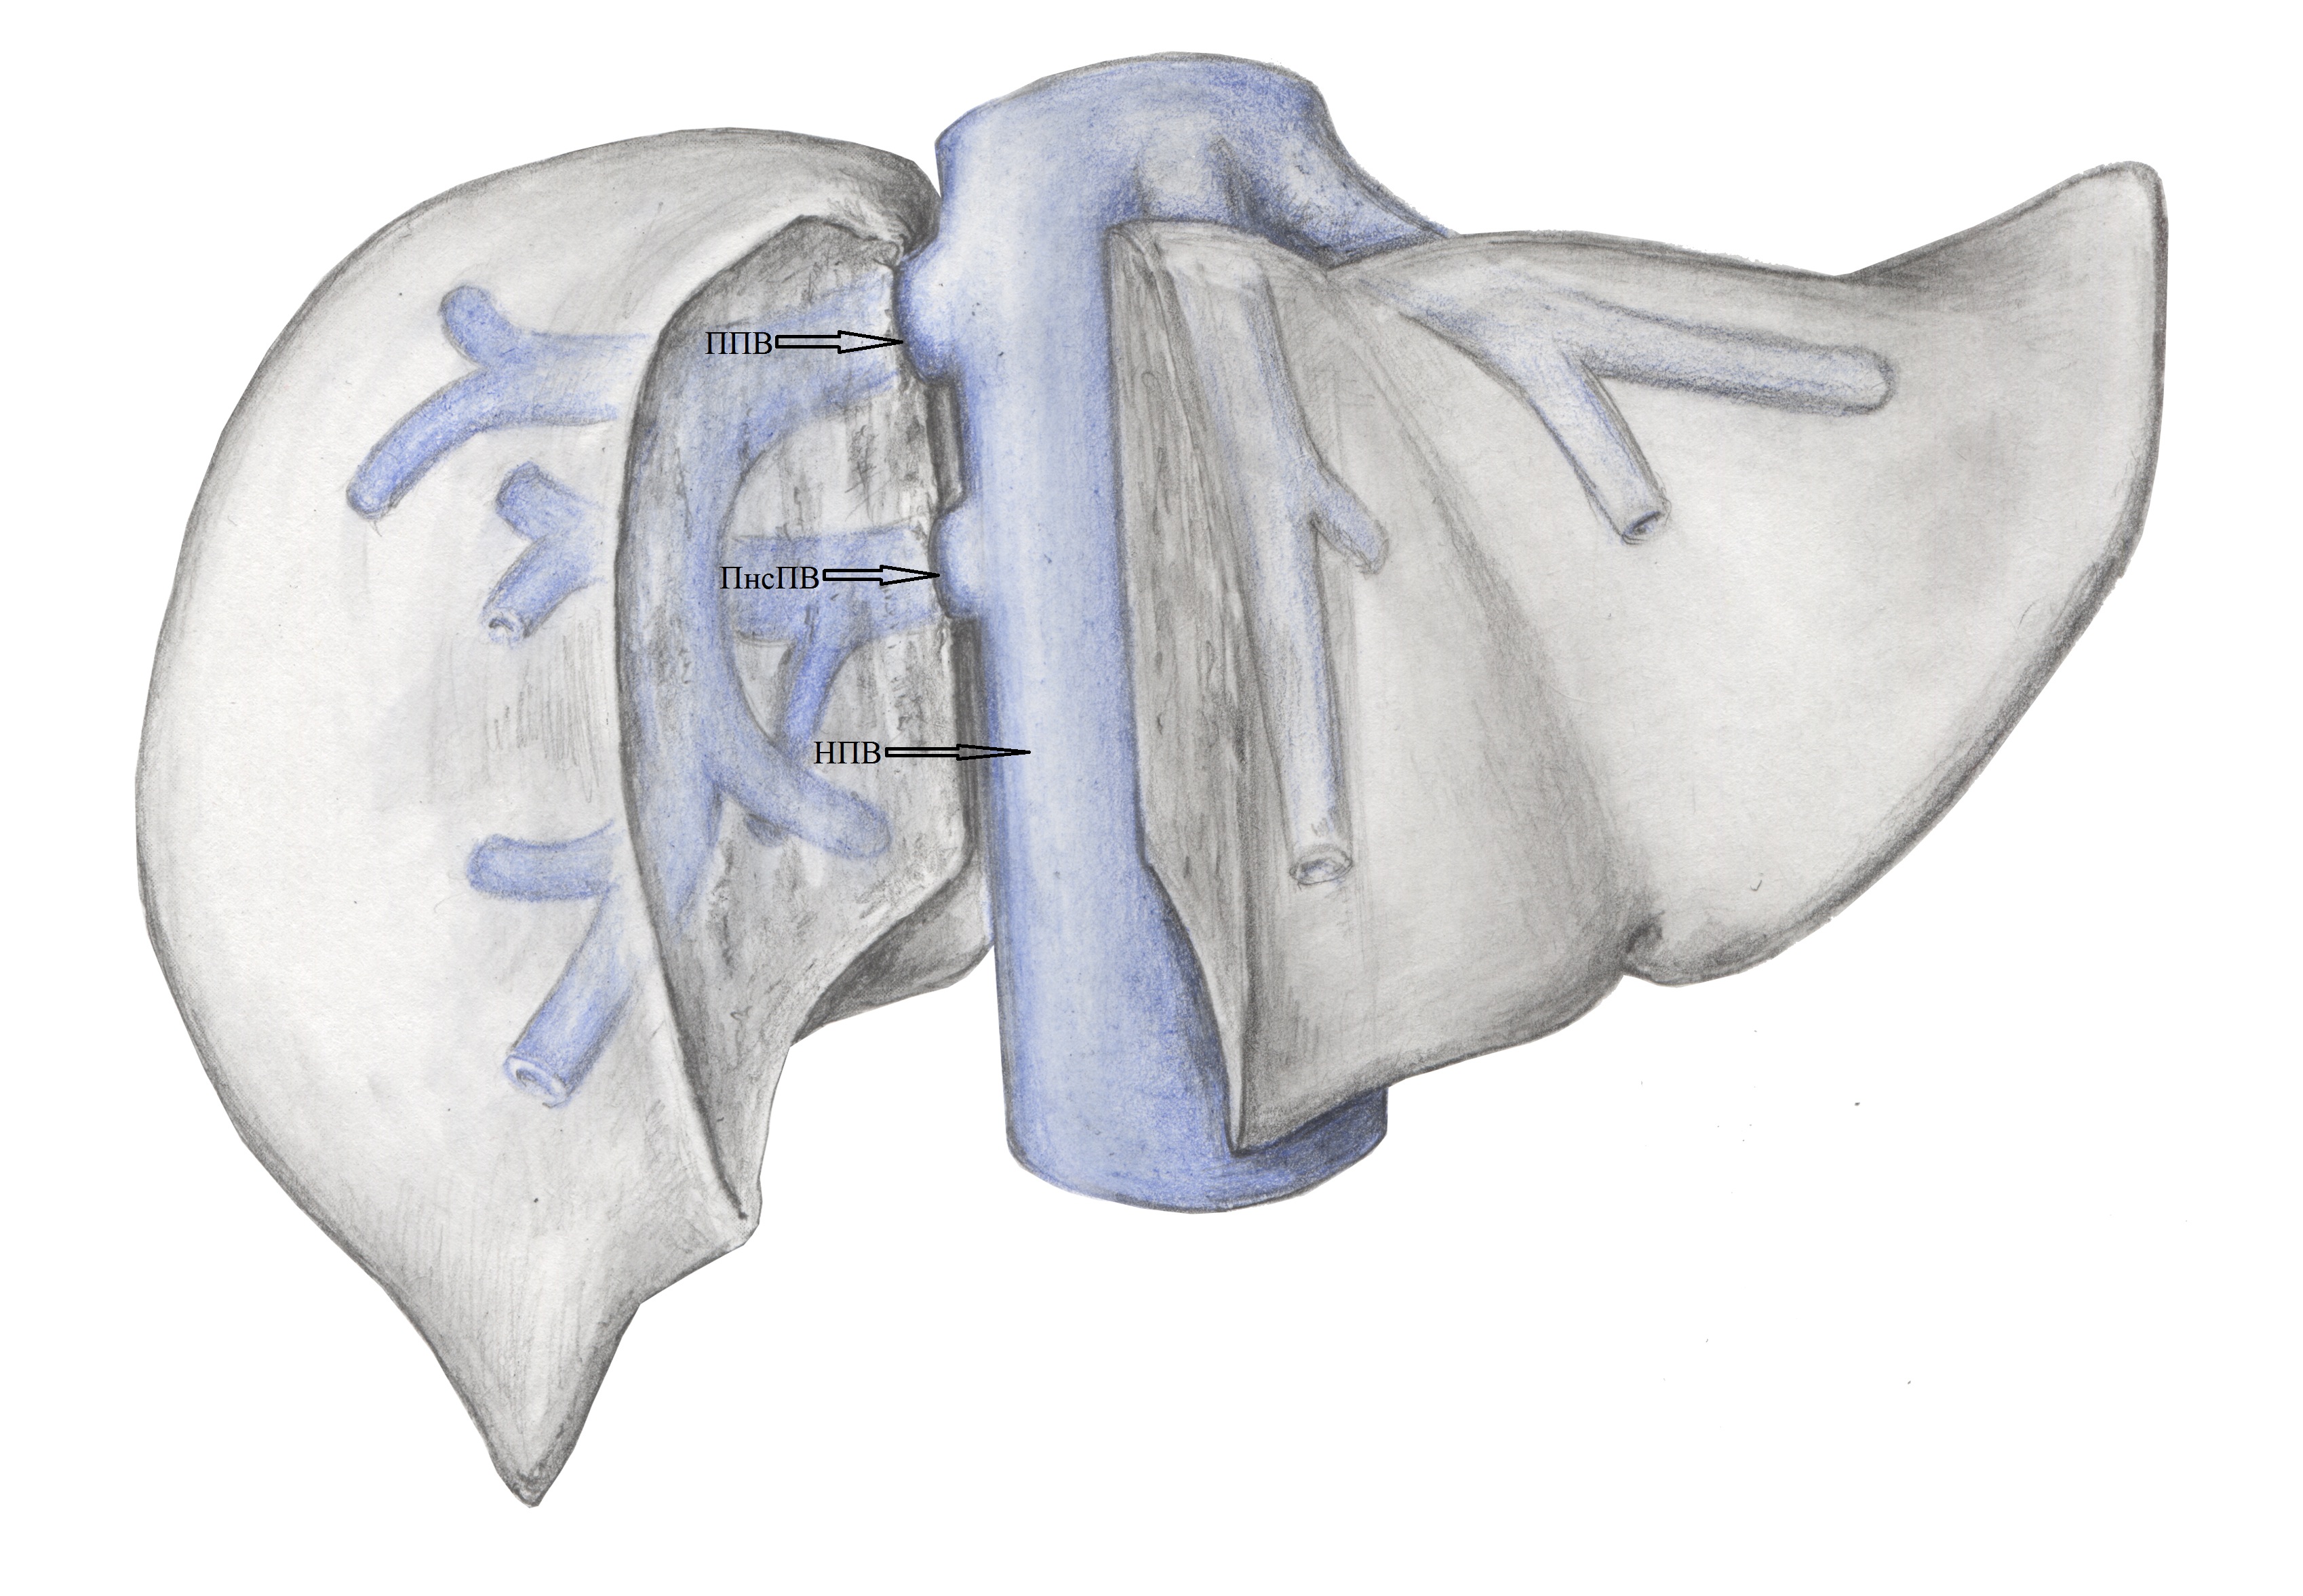

2. Тип А (схема). | |

| Тема | ||

| Тип | Исследовательские инструменты | |

Посмотреть

(1MB)

|

Метаданные ▾ | |